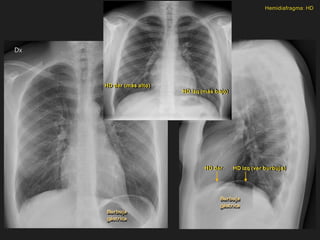

HD der (más alto)

HD izq (más bajo)

HD izq (ver burbuja)

HD der

Hemidiafragma: HD